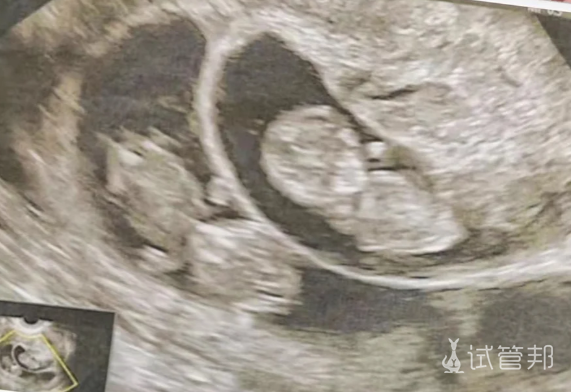

说到双胞胎,还有同卵和异卵之分呢。同卵双胞胎就是一个受精卵分裂出来的,长得那叫一个像,有时候真分不清谁是谁;而异卵双胞胎就是两个不同的卵子分别受精的,长相上就有区别了,挺好认的。

- #同卵双胞胎